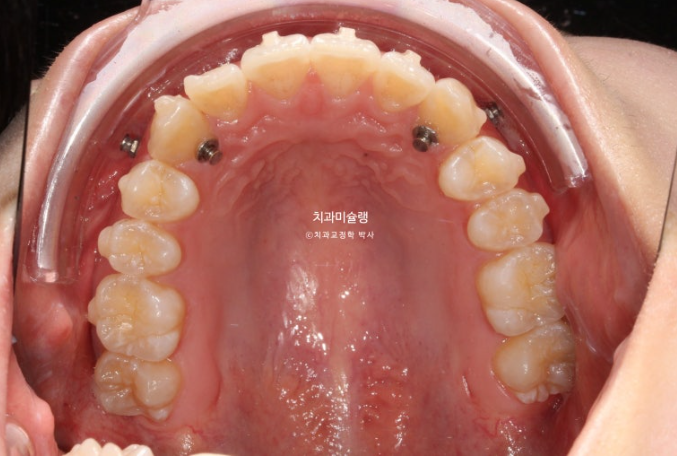

또한 웃을때 잇몸도 보이는 편이라 교정용 나사를 심고 앞니 함입도 도모했습니다.

14개 장치를 2월부터 6월까지 모두 낀 후 모습입니다.

중심선은 상당히 개선되었으며 덧니는 잘 배열 되었습니다.

송곳니 주변에 공간이 남아있으며

덧니 배열이 완벽하진 않습니다.